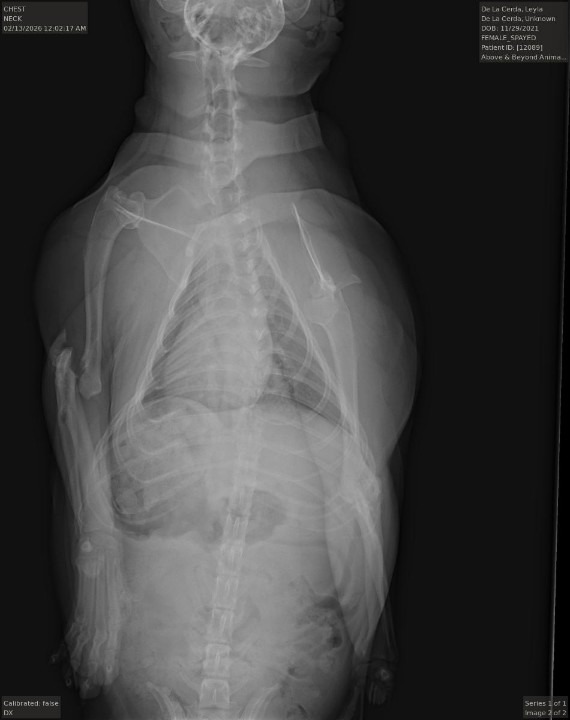

On February 12, when I was going outside, she ran out fast and through our front gate into the street, a car drove and kept driving, hitting her without stopping, all of this happened so fast. She is alive, but now has suffered a dislocated elbow and fracture injury. Taking her to the emergency pet hospital, this bill is going to be very expensive.